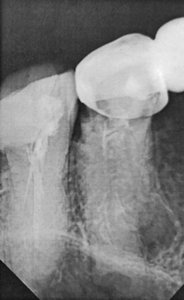

У меня коренной 7-й зуб сверху раскололся на две части вертикально, корневые каналы запломбированы. Удалять или можно вылечить зуб?

• Снимок недостаточно хорошего качества. Если перелом вертикальный и затрагивает корень, то зуб подлежит удалению.